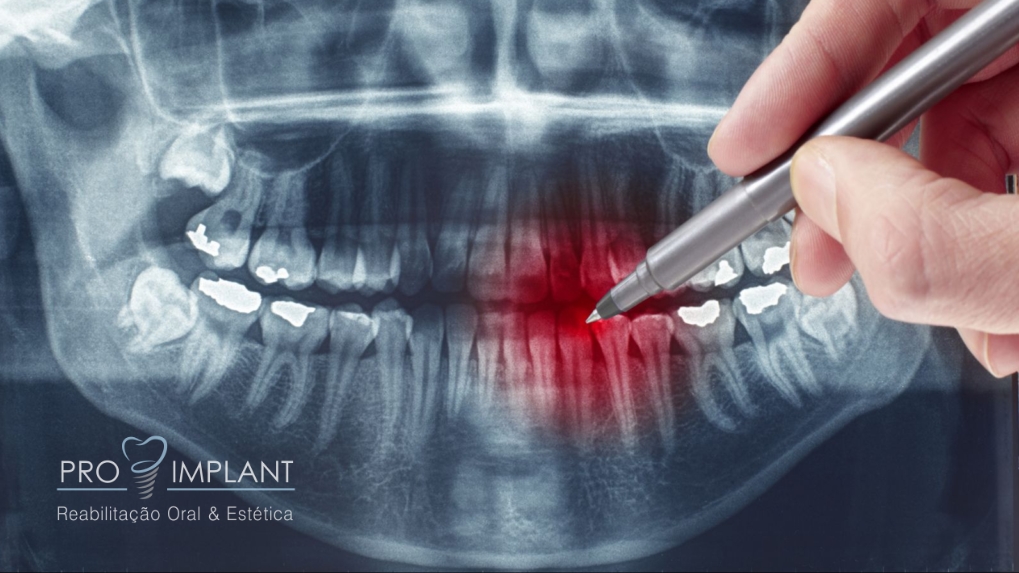

Dentre estes procedimentos podemos destacar: exodontia de terceiros molares (dentes do siso), cirurgias para remoção de pequenas lesões, cirurgias pré-protéticas, entre outras. As Cirurgias Orais são muitas vezes a solução para um bom resultado.